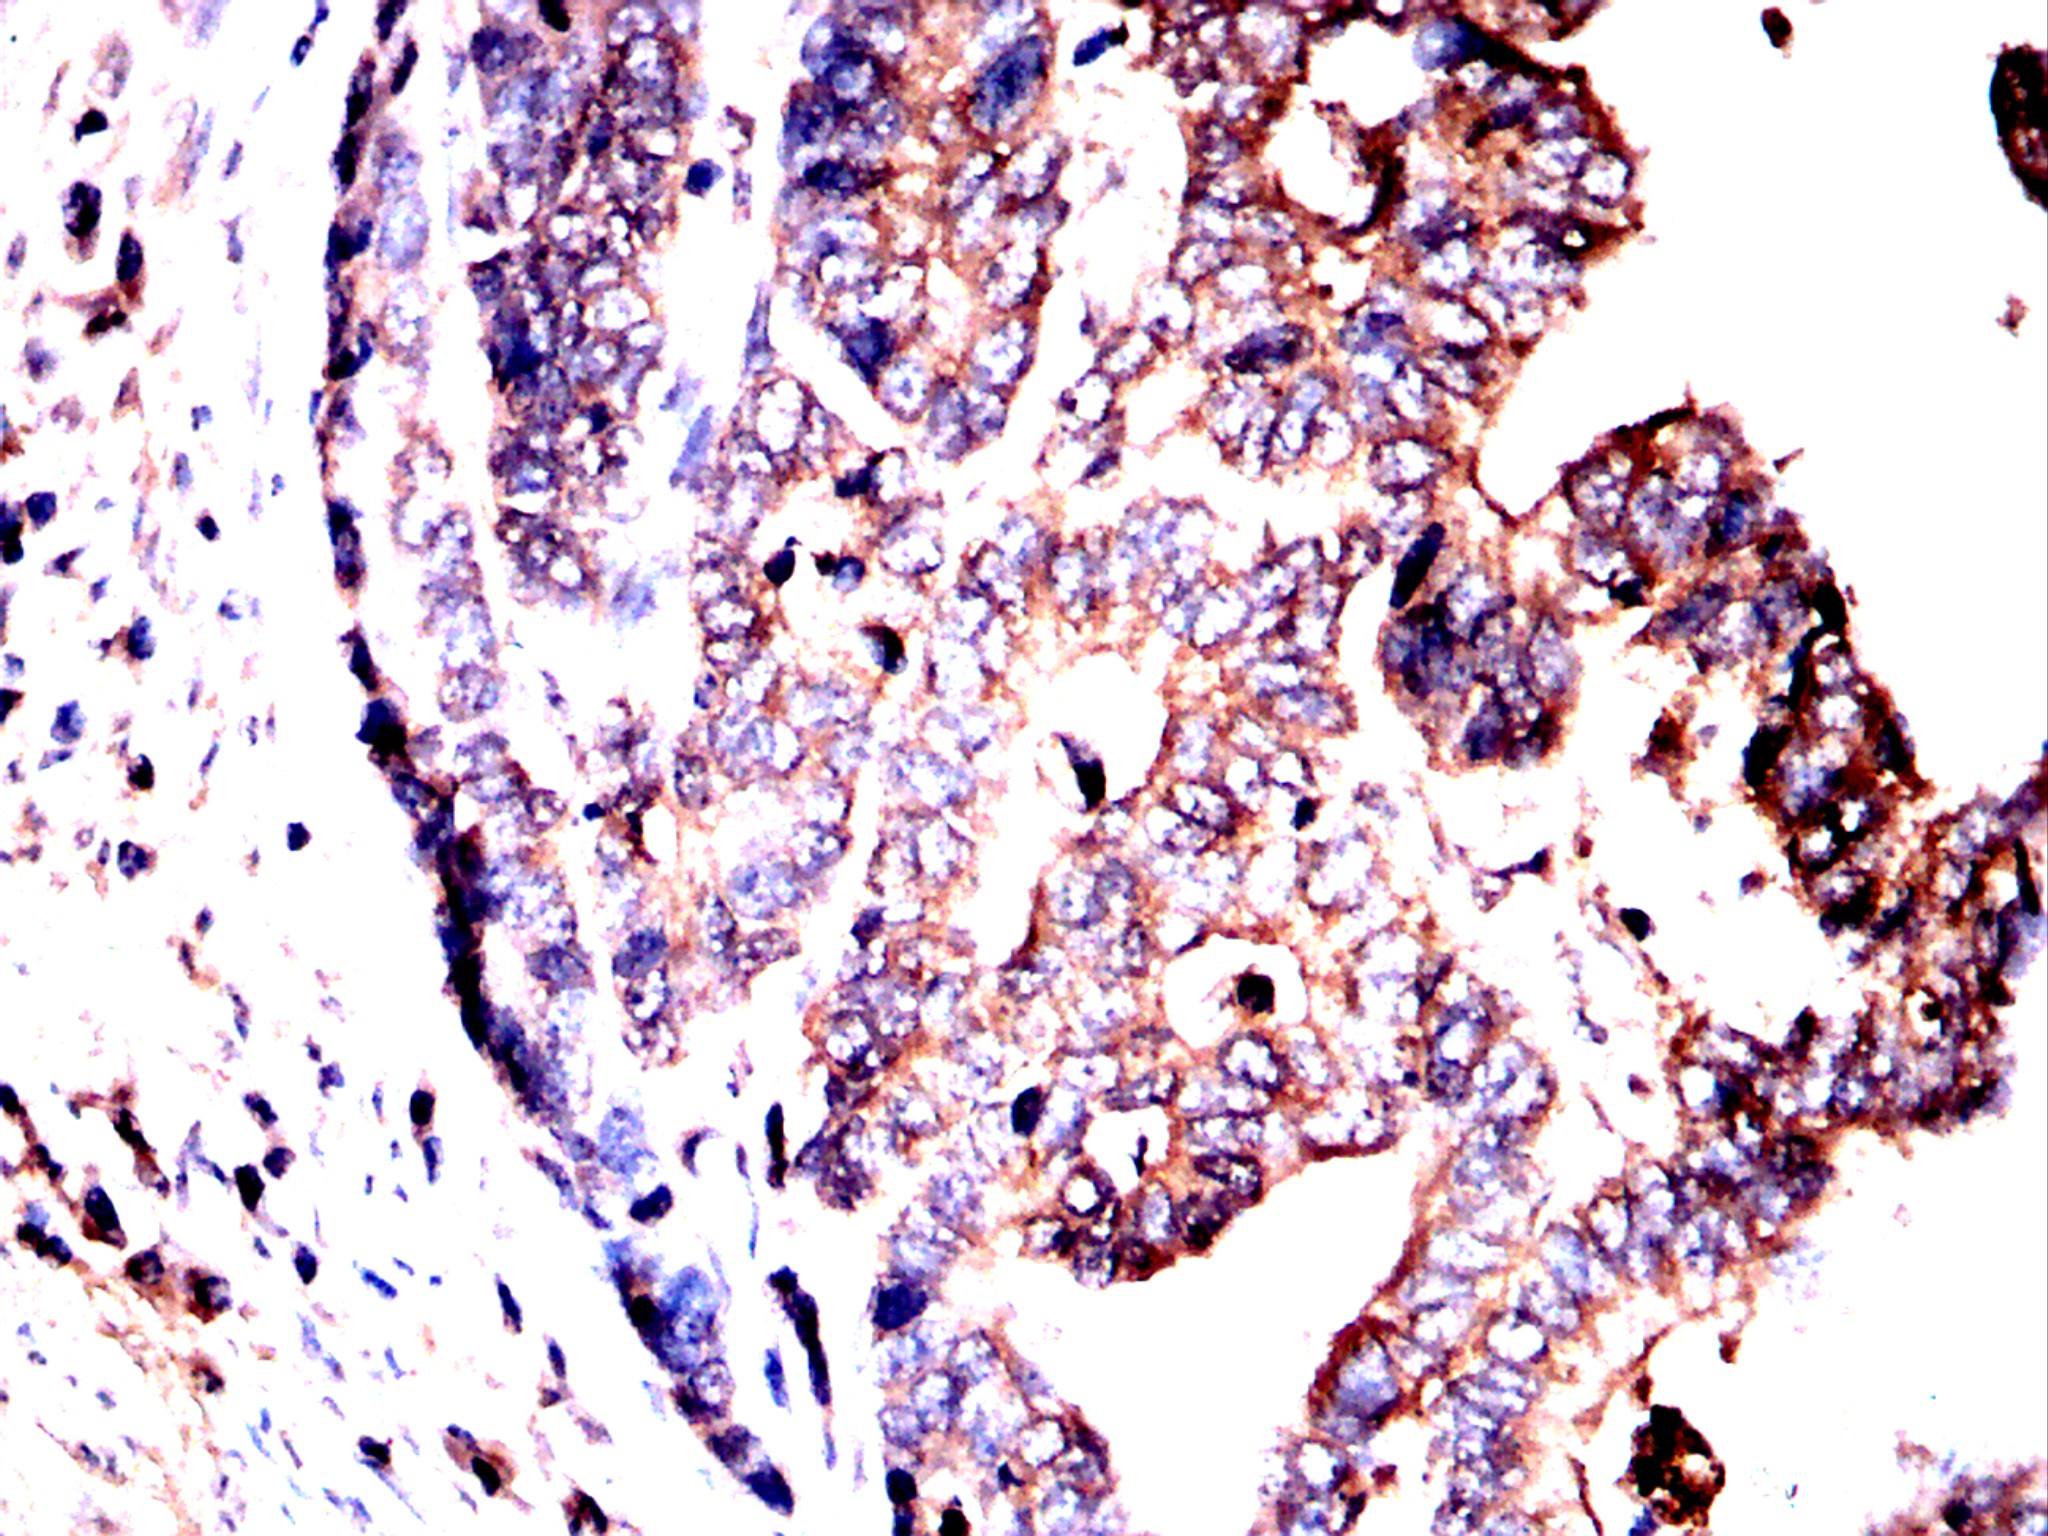

Immunohistochemical analysis of paraffin-embedded bladder cancer tissues using VTI1B antibody with DAB staining. Pre-treat the sections with heat-mediated antigen retrieval using sodium citrate buffer (pH 6.0) (OM750020) for 2 minutes. Wash the sections with ddH₂O and PBS (OM750003). Block the tissue with 10% non-immune goat serum(OM760028) at room temperature for 30 minutes. Incubate the tissue with the primary antibody diluted at a ratio of 1:1500 at 4°C overnight. At room temperature, dilute the secondary antibody, Goat Anti-Rabbit IgG(H&L)-HRP (OM644332), at a ratio of 1:200 and incubate for one hour. Use DAB(OM760029)as the chromogenic agent. Counterstain the tissue with hematoxylin, and mount the tissue sections with neutral gum.IHC

Immunohistochemical analysis of paraffin-embedded bladder cancer tissues using VTI1B antibody with DAB staining. Pre-treat the sections with heat-mediated antigen retrieval using sodium citrate buffer (pH 6.0) (OM750020) for 2 minutes. Wash the sections with ddH₂O and PBS (OM750003). Block the tissue with 10% non-immune goat serum(OM760028) at room temperature for 30 minutes. Incubate the tissue with the primary antibody diluted at a ratio of 1:1500 at 4°C overnight. At room temperature, dilute the secondary antibody, Goat Anti-Rabbit IgG(H&L)-HRP (OM644332), at a ratio of 1:200 and incubate for one hour. Use DAB(OM760029)as the chromogenic agent. Counterstain the tissue with hematoxylin, and mount the tissue sections with neutral gum.